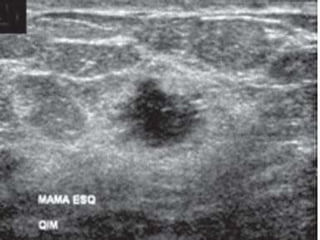

Além da mamografia existem ainda outros meios de

diagnóstico de câncer de mama além da mamografia, tais

como ressonância magnética, ultrassonografia e

tomossíntese.

ULTRASSONOGRAFIA

Além da mamografiaexistem ainda outros meios de diagnóstico de câncer de mama além da mamografia, tais como ressonância magnética, ultrassonografia e tomossíntese.